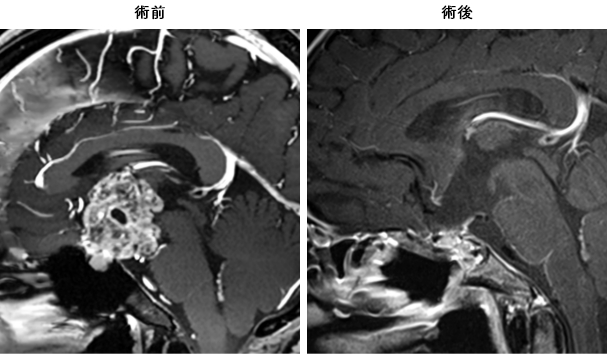

頭蓋咽頭腫

たいへん大きな腫瘍ですが、内視鏡により全摘出することができた患者さんです。ただし、周囲の重要な血管や神経と強く癒着しているときにはどうしても完全摘出を行うことが難しい場合があります。摘出率にこだわりすぎないで、ガンマナイフなど放射線治療を組み合わせた慎重な治療プランが必要です。